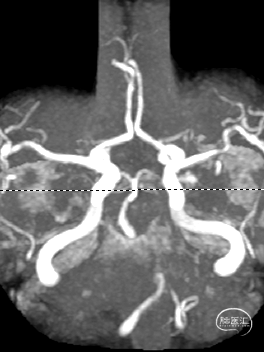

MR:双侧后循环散在急性梗死病灶(双侧小脑半球、双侧枕叶、胼胝体压部、右侧脑桥臂、桥脑右侧部及中脑被盖左侧)。MRA示:双侧椎动脉颅内段及基底动脉明显变窄。

CTA:椎基底动脉连接处重度狭窄;多发脑动脉狭窄。